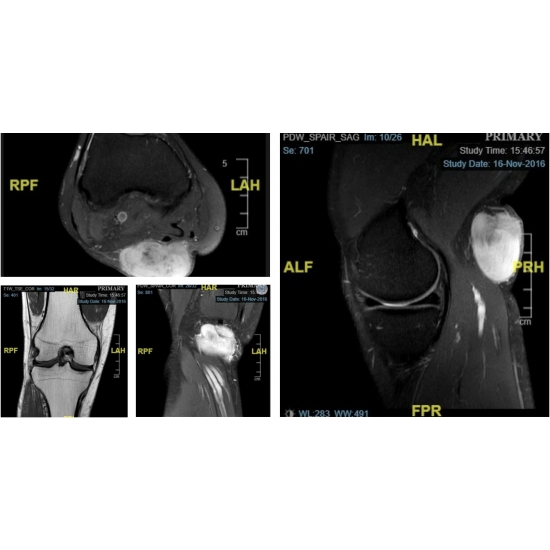

A lateral radiograph of the right knee was done and revealed a posterior soft tissue mass Case Photo #2 . An anterior-posterior view of the bilateral knees was done and did not appreciate any joint space narrowing. Subsequently, a magnetic resonance imaging (MRI) of the right knee was done and revealed a 5.1 x 4.3 x 3.0 cm peripherally enhancing mass involving the posterior right knee subcutaneous soft tissues that was considered to be a primary soft tissue sarcoma (STS) Case Photo #3 . A biopsy of the right popliteal protrusion was done and the pathology was positive for a stage 1 grade IB fibrosarcoma